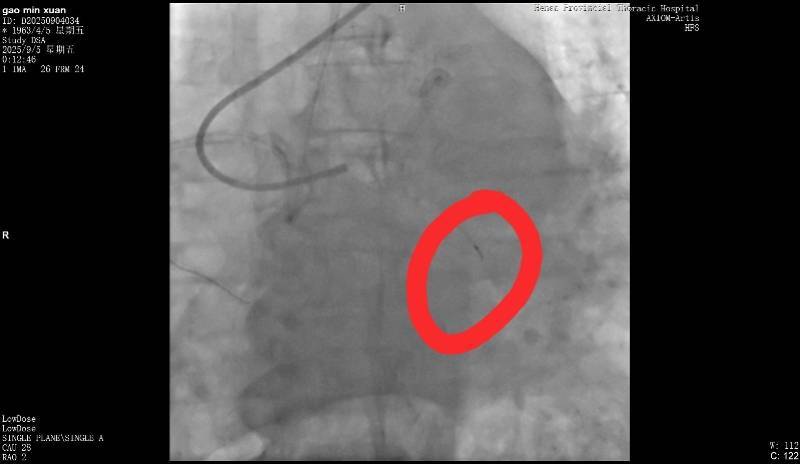

断裂的导丝皇冠信用网在线注册。受访者供图

9月5日,高女士父亲在该医院做冠脉造影,手术进行了近3个小时皇冠信用网在线注册。高女士回忆说,手术结束后,负责手术的医生告诉她,“在微创探查体内的时候,一截导丝断裂。”当高女士询问能否再次实施手术取出时,医生表示因病患年纪较大,开胸手术存在危险,并没有取出的必要。但对于遗留导丝会否在后续造成长期影响,该医生则称“无法确定”。

高女士提供的病程记录显示,“手术操作过程中出现回撤导丝困难,送入微导管尝试至坎顿处未成功,退出微导管时远段导丝断裂,多途径尝试取出断裂导丝均未能成功皇冠信用网在线注册。”资料还指出,“通过复查造影,回旋支近段残余狭窄小于30%,未见明显夹层、无复流。”

南都记者留意到,该病程记录给出了心血管外科一病区会诊意见,称“回旋支内见离断的介入导丝,外科取出导丝意义不大,建议内科治疗”皇冠信用网在线注册。

该医患办工作人员向南都记者解释称,术后院方组织了相关科室会诊,判断回旋支指引导丝远段断裂,与患者回旋支弥漫性动脉硬化重度狭窄病变及钙化有关皇冠信用网在线注册。“如果患者需要做医疗事故鉴定,院方将全力配合。如果对方经济困难,医院愿意垫付费用做鉴定。”其还表示,医院将根据第三方相关鉴定,承担院方该承担的责任。